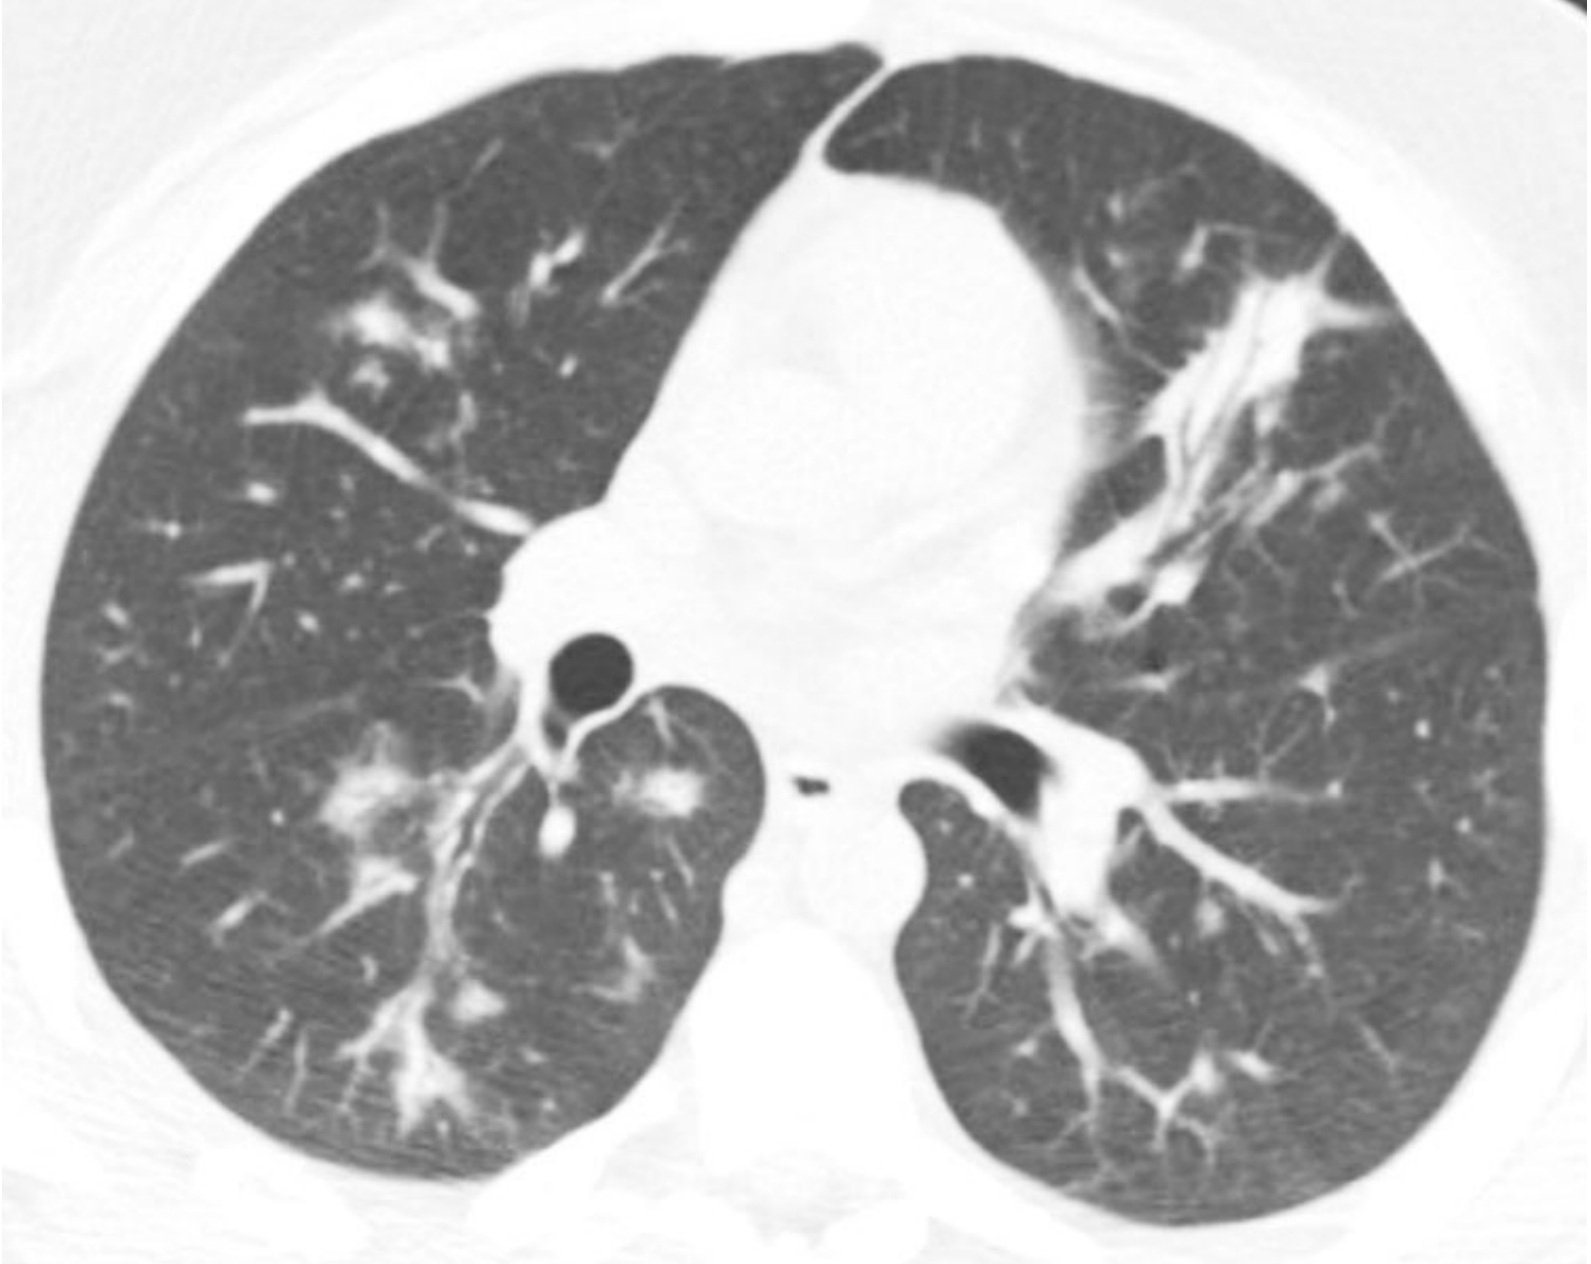

间质性肺炎的HRCT表现取决于炎症或者纤维化的程度。以炎症为主的病例表现为磨玻璃影(GGO)和(或)实变。以纤维化为主的病例表现为不规则网状影、牵拉性支气管扩张和(或)蜂窝征。

虽然在某些病例中可能存在明显的炎症和纤维化成分,但是大部分间质性肺炎通常以两者之一为主要表现。普通型间质性肺炎(UIP)以肺纤维化为主要特征,非特异性间质性肺炎则可能表现为纤维化型或细胞型或两者兼有。其余的间质性肺炎则以炎症为主,但是部分病例可能向纤维化进展。

eb8e21eebff9ef7cc5bf91aa43df6ecf.png

炎症与纤维化的HRCT不同表现。

间质性肺炎表现为不同程度的炎症和纤维化;A和B. 2例结缔组织病患者的非特异性间质性肺炎。

A.HRCT显示GGO,无明显的纤维化征象,提示潜在可逆的炎症性病变;

B.HRCT显示牵拉性支气管扩张(箭)及不规则网状影的纤维化征象,提示对治疗不敏感的肺部瘢痕。